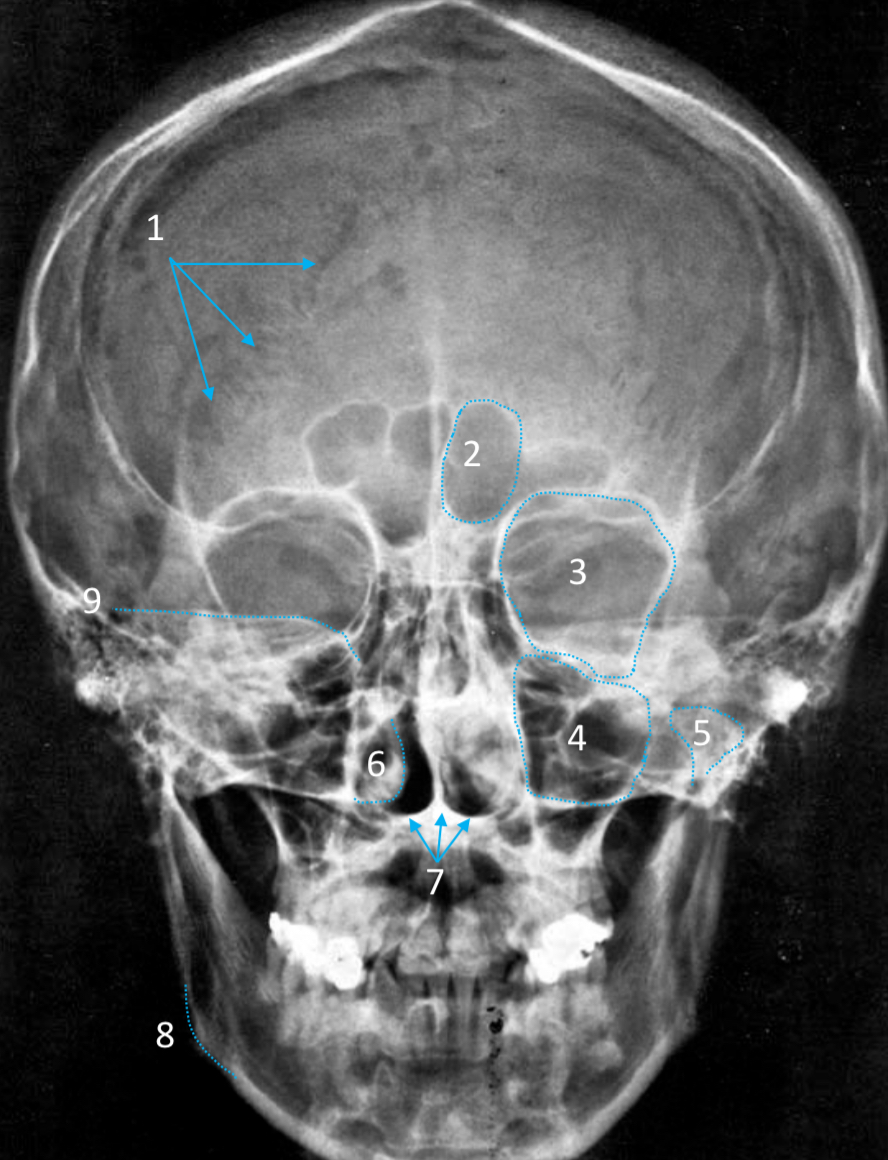

Frontal sinus

ID structure

Pituitary fossa

ID structure

Frontal sinus

ID structure

Orbital margin

Orbit

Maxillary sinus

ID structure

Mandibular condyle

ID structure

Inferior nasal concha

ID structure

Hard palate

ID strucutre

Gonial angle

ID strucutre

Petrous ridge

ID structure

Groove of middle meningeal a.

ID structure

Roof of orbit

ID structure

Frontal sinus

ID structure

Pituitary fossa

ID structure

Petrous ridge

ID structure

Sphenoid sinus

ID structure

Hard palate

ID structure

Mastoid air cells

ID structure

Zygomatic arch

ID structure

Mandibular condyle

ID structure

External auditory meatus

ID structure

Mastoid air cells

ID structure

Foramen magnum

ID structure

Foramen ovale

ID structure

Foramen spinosum

ID structure